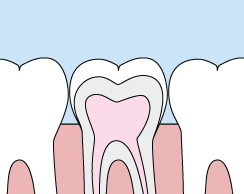

Crowns

Crowns are a cosmetic restoration used to improve your tooth’s shape or to strengthen a tooth. Crowns are most often used for teeth that are broken, worn, or have portions destroyed by tooth decay.

A crown is a "cap" cemented onto an existing tooth that usually covers the portion of your tooth above the gum line. In effect, the crown becomes your tooth’s new outer surface. Crowns can be made of porcelain, metal, or both. Porcelain crowns are most often preferred because they mimic the translucency of natural teeth and are very strong.

Crowns or onlays (partial crowns) are needed when there is insufficient tooth strength remaining to hold a filling. Unlike fillings, which apply the restorative material directly into your mouth, a crown is fabricated away from your mouth. Your crown is created in a lab from your unique tooth impression, which allows a dental laboratory technician to examine all aspects of your bite and jaw movements. Your crown is then sculpted just for you so that your bite and jaw movements function normally once the crown is placed.